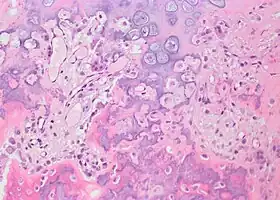

Histopathology

Bone Bizzare Parosteal Osteochondromatous Proliferation -

Bone Bizzare Parosteal Osteochondromatous Proliferation